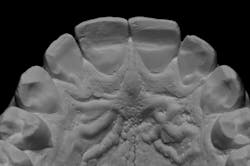

We always complete treatment on our models before we ever begin treatment on our patients, so that we are confident we can achieve the same result in the mouth. Below you will see that we completed a minimal wax-up to recontour the gingival levels and correct proportions and contours. We also worked out Dawson’s 5 requirements of occlusal stability by utilizing equilibration and refining the anterior guidance with our proposed restorations.

These models (figures 7–10) can then be sent to the laboratory for fabrication of the final wax-up, reduction guides, and provisional matrices. In contrast, we could also scan these models and upload the files to perfect our digital wax-up.